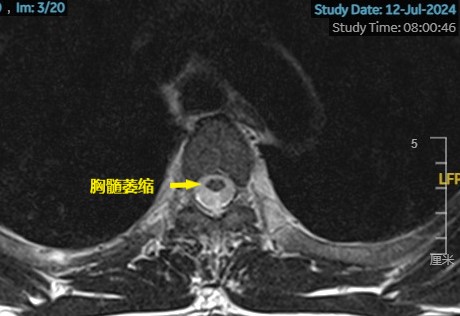

脊柱磁共振提示:胸段脊髓萎缩。